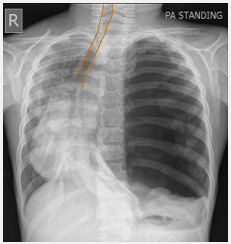

Name the CXR finding in this CXR [1]

diaphragm elevation